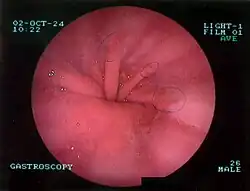

Upper GI endoscopy depicting hiatal hernia -